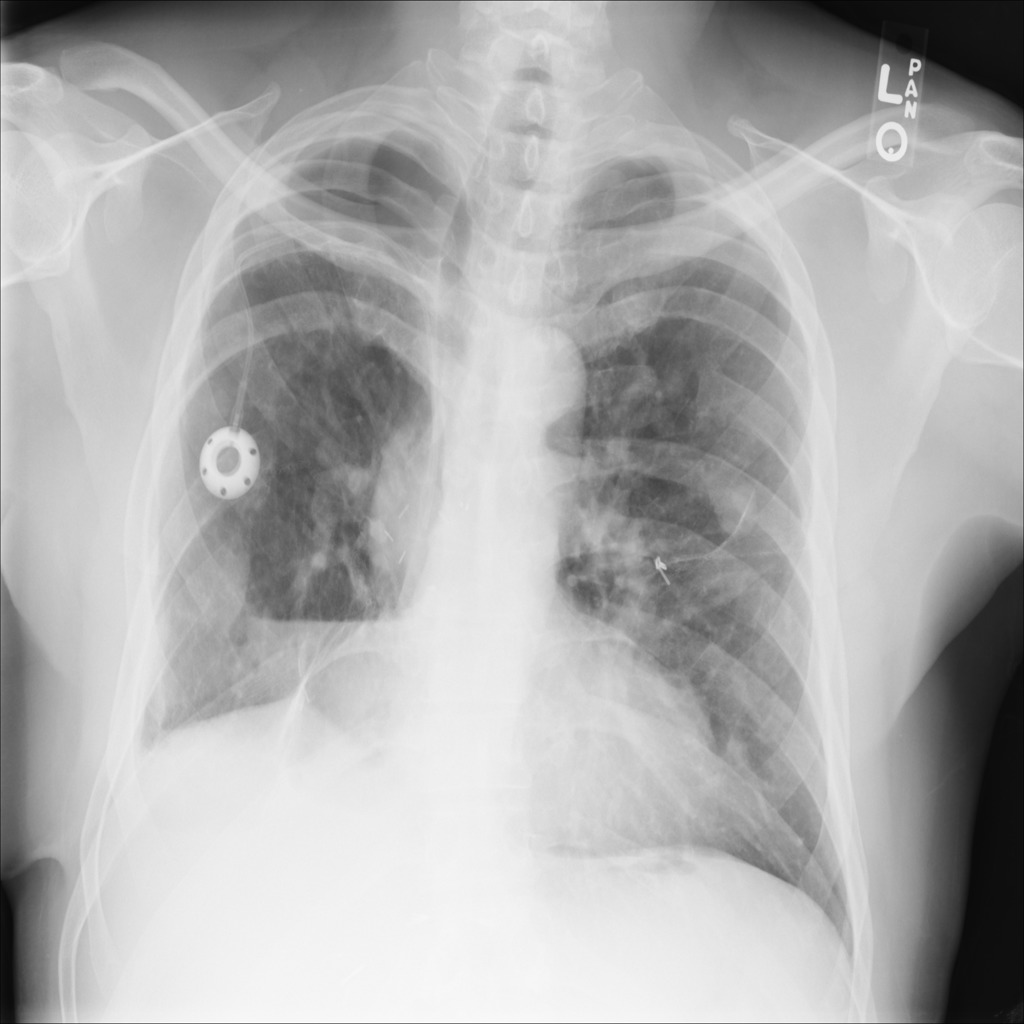

Refer to caption

(a) Image

(b) Step1.CAM

Figure 2: Segmentation predictions for (a) a random image from test set of SIIM-ACR Pneumothorax produced at each step of our approach: (b) CAM extraction, (c) IRNet, (d) U-Net segmentation, compared to (e) ground truth mask.

We present method’s explainability via disease localization regions; cf. Figure 1. We provide qualitative results of segmentation on validation images from both datasets in Figure 2 and Figure 3. We show the resulting maps at each step of our method; the figures demonstrate how the performance improves after each step. We achieve comparable results to state-of-the-art method on PASCAL VOC 2012; cf. Table 4.